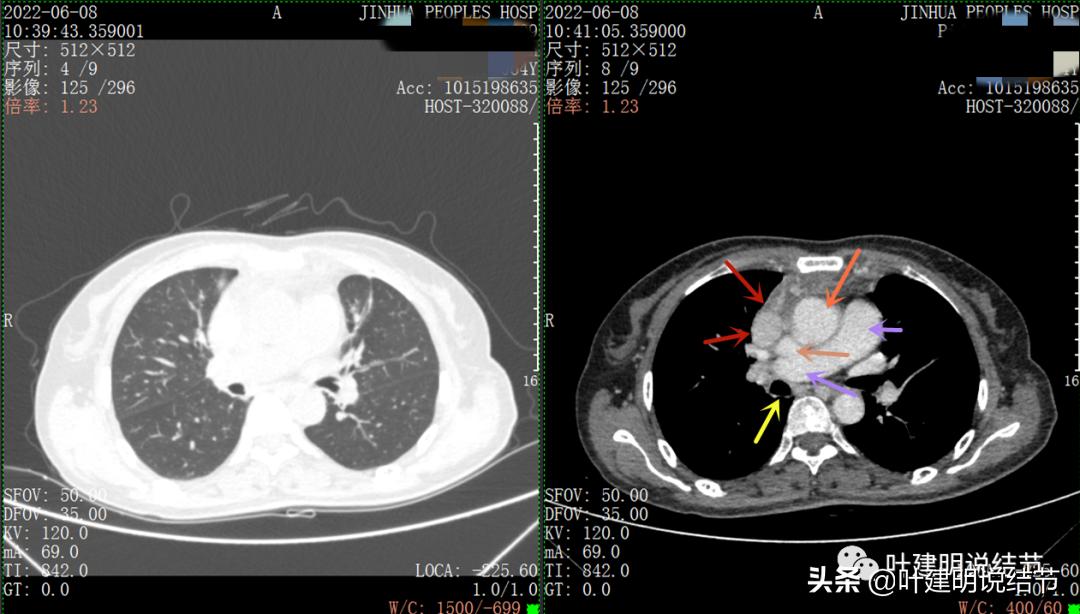

再来看看她的CT增强图像:

以下图片左侧是肺窗,右侧是纵隔窗。红色箭头示病灶,桔色箭头示无名静脉,黄色箭头示支气管,砖色箭头示上腔静脉,蓝色箭头示主动脉,紫色箭头示肺动脉。

病灶胸顶较高位置就出现了,在无名静脉水平

无名静脉略受压